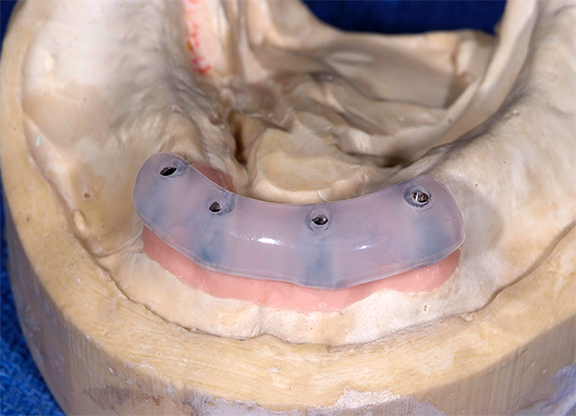

If a new denture is to be made, scan bodies may be snapped over the attachments and impressions may be made, with records registered and then sent to the laboratory for fabrication of a new prosthesis.41 To convert the digital/existing dentures to implant-supported overdentures, the dentures were relieved in the location of the implants and the denture caps were picked up chairside in the dentures.41 An interocclusal record was made with a bite registration material and placed in the mouth to guide the patient in centric closure during the relieving of the denture and the chairside pickup of denture caps. The occlusal vertical dimension was recorded before relieving the dentures and kept constant during the pickup of the denture caps.41

To adequately relieve the denture in the area of the implants, an impression and bite registration material was placed on the intaglio surface of the prosthesis, and then the prosthesis was placed over the overdenture abutments.41 The prosthesis was removed from the mouth after the polymerization of the impression material. The indentations of the denture caps were registered in the impression material (Figure 13). A vent hole bur was used to drill straight through the center of the indentations (Figure 14, top).41 A recess bur that fitted right in the hole was used to open the spaces (Figure 14, bottom). Next, retention was created by using an inverted cone retention bur.41 Then a round bur, football-shaped bur, and polisher were used to finish and polish the recesses.41